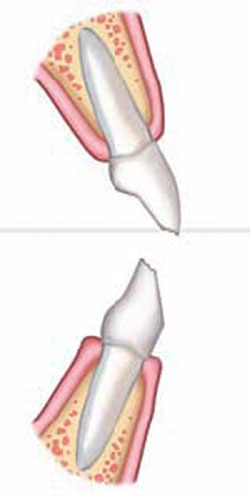

The 10-year-old patient shown in Figure 3A initiated orthodontic treatment at a young age when multiple permanent teeth were found to be congenitally missing, a condition termed oligodontia (severe partial anodontia). Oligodontia is characterized by the congenital absence of more than six permanent teeth, excluding third molars.11 Patients with the condition may have severe psychological problems12 related to an unesthetic smile, which is from missing and small teeth and resulting diastemas in the dentition.13 Functionally, a posterior cross-bite had developed in this patient, probably resulting from alveolar bone underdevelopment in the absence of the eruption process of the missing permanent teeth roots14 (Figure 3A and Figure 3B). In such cases, early intervention and space management with dentofacial orthopedics by the orthodontist is appropriate.2

The orthodontist carefully managed this case for several years. Rapid palatal expansion therapy, reverse-pull headgear treatment, and space maintenance were employed to influence growth and development until implant therapy and restorative treatment could begin, minimizing the potential negative consequences of no treatment (Figure 3C). The remaining permanent incisors were smaller than normal,13 and the upper primary lateral incisors were scheduled for extraction. After positioning the upper central incisors as close to ideal as possible, the orthodontist requested intermediate restoration of the upper anterior teeth. The permanent first premolars were positioned in the cuspid locations for conversion to cuspids, thereby preventing problems associated with adjacent implants in the esthetic zone. Given the major tooth-size and space discrepancies in this case, more traditional composite-resin buildup procedures were impractical for intermediate restorations.

Denture teeth, carefully selected for size and shape, can be reshaped and hollow-ground to resemble veneers (Figure 3D). Similar methods have had good success when used to design implant provisional crowns. This procedure can be performed most efficiently on a diagnostic model in the laboratory to save valuable chair-time. The laboratory steps are tedious, requiring multiple trials and adjustments. It is important that the clinician positions the denture tooth veneers along the long axes of the teeth and resists the temptation to correct misalignments restoratively. This represents one of the more difficult aspects of intermediate restorations for the restorative dentist who, by training, normally restores teeth to the existing occlusion and adjacent tooth structures. Instead, he or she should build to ideal individual tooth anatomy and then allow the orthodontist to correct the proper occlusal and arch-form relationships.

In this case, the plan created during the model-preparatory work was to recontour the soft tissues because of slightly redundant gingival tissues and to remove the primary lateral incisors. The denture teeth were trimmed, thinned, and luted precisely onto the model with block-out compound, and then the positions were registered in a putty silicone index15,16 to facilitate transfer to the mouth (Figure 3E).17 The margins of the veneers are very thin as seen in Figure 3E. The silicone index allows the visualization of the veneer seating process, thereby ensuring proper adaptation to the teeth and easier cleanup. The teeth were prepared very slightly at the line-angles and etched for bonding in the same fashion as conventional veneers. Warmed composite resin (to increase flow)9 was loaded into the denture tooth veneers and pressed onto the teeth. Excess composite resin was removed, and then the veneers were light-cured, finished, and polished. Radiosurgery created a more desirable soft-tissue profile in relationship to bone and to maintain a healthy biologic width.18 The primary lateral incisors were extracted, and the matching denture tooth lateral incisors were sent to the orthodontist for use as pontics on the arch-wire (Figure 3G).

Figure 3A A 10-year-old patient with oligodontia, missing multiple permanent teeth. Retracted view shows posterior cross-bite, resulting from underdeveloped alveolus. |  Figure 3B Panoramic radiograph shows retained primary teeth, eight missing permanent teeth, and delayed eruption pattern. | ||||||

Figure 3C Orthodontics and dentofacial orthopedics were performed to develop arches for optimal future restorative.Mini-implants were used for orthodontic anchorage. |  Figure 3D Denture teeth hollow-ground and luted to model along the long axes of the teeth. Lateral incisors will be extracted. | ||||||